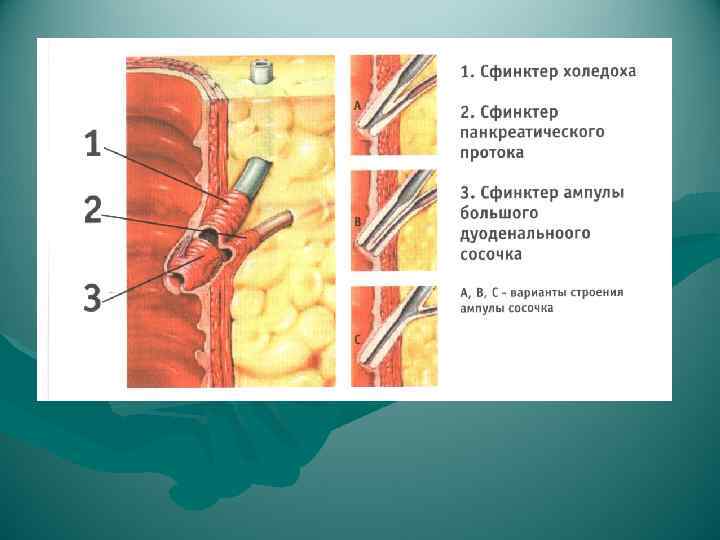

ВИДЫ ОПЕРАЦИЙ НА ЖЕЛЧНЫХ ПУТЯХ 1. Холецистотомия 2. Холецистостомия 3. Холецистэктомия - от дна (антеградная) преимущество • надежная идентификация отдельных элементов шейки пузыря недостаток • большая кровоточивость - от шейки (ретроградная) преимущество • малая кровоточивость при выделении желчного пузыря (перевязка a. cystica); • предотвращается возможность проталкивания мелких камней из пузыря в ductus choledochus (перевязка d. cysticus) - комбинированный способ 4. Холецистоэнтеростомия 5. Холедохотомия - эксплоративная (во время холецистэктомии) - трансдуоденальная 6. Холедоходуоденостомия 7. Папиллосфинктеротомия

ВИДЫ ОПЕРАЦИЙ НА ЖЕЛЧНЫХ ПУТЯХ 1. Холецистотомия 2. Холецистостомия 3. Холецистэктомия - от дна (антеградная) преимущество • надежная идентификация отдельных элементов шейки пузыря недостаток • большая кровоточивость - от шейки (ретроградная) преимущество • малая кровоточивость при выделении желчного пузыря (перевязка a. cystica); • предотвращается возможность проталкивания мелких камней из пузыря в ductus choledochus (перевязка d. cysticus) - комбинированный способ 4. Холецистоэнтеростомия 5. Холедохотомия - эксплоративная (во время холецистэктомии) - трансдуоденальная 6. Холедоходуоденостомия 7. Папиллосфинктеротомия